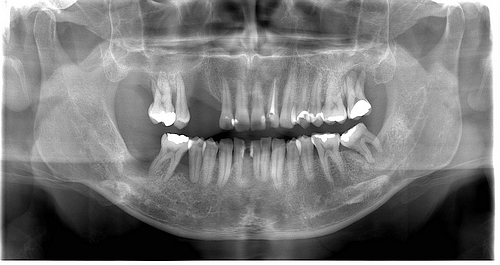

DÖRT BOYUTLU AYRINTILI İKİNCİ DÜZEY DETAYLI RENKLİ DOPPLER ULTRASONOGRAFİ MAMOGRAFİ KEMİK YOĞUNLUĞU PANORAMİK SEFALOMETRİK RÖNTGEN GÖRÜNTÜLEME MERKEZİ İSTANBUL ATAŞEHİR KAVACIK